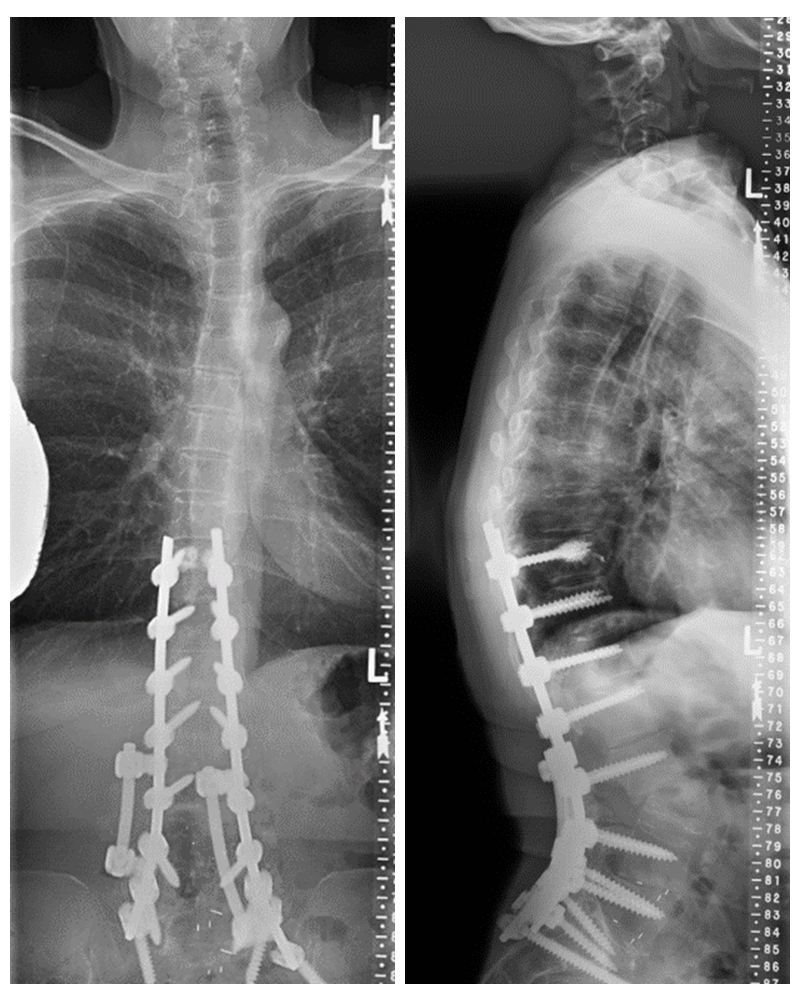

术前X线

予患者行后路PSO截骨,T10-骨盆固定。

术后X线